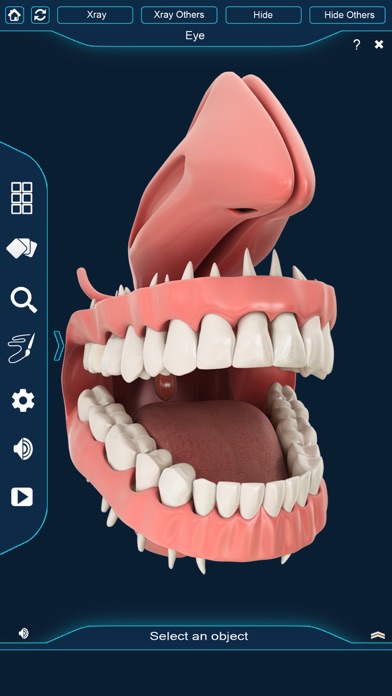

My Dental Anatomy app for studying human Dental Anatomy which allows you to rotate 360° , Zoom and move camera around a highly realistic 3D model.

My Dental Anatomy app gives users an in depth look at the human Teeth allowing them to select , x-ray view, hide and show individual tooth Parts as well as , draw or white on screen and share screenshots, Audio pronunciation for all anatomical terms and more.

Tooth Anatomy such As

Molar

Gum

premolar

canines

lateral incisor

central incisor

uvula

-Highly realistic Dental Anatomy 3D models.